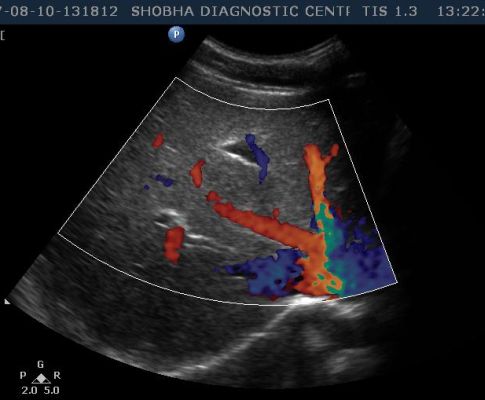

- Abdominal Doppler

- PELVIS

- UTERINE / OVARIAN VESSELS

- PELVIC MASS

In color Doppler the blood circulation is assessed. It is more often done in diabetic patients, in chronic smokers who are more prone to develop blockage in their arteries, in patients who suffer from varicose vein problem.

It is non invasive test which tells you about blood circulation to any particular part of the body like upper limb, lower limb, blood supply to any tumor or swelling involving the body.